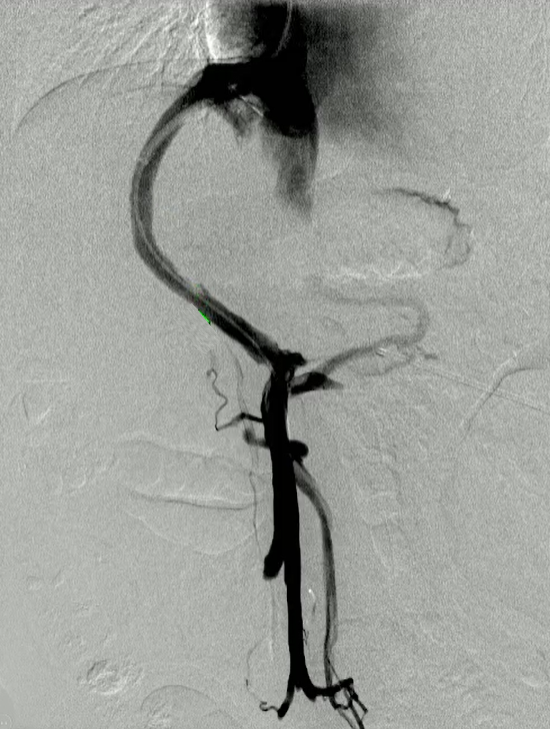

该程序包含以下步骤: 经脾脏入路:在超声引导下,刺穿脾静脉内的一个实质内分支。 在通过脾静脉造影确认了静脉通路后,导管和导丝被推进,以穿过脾静脉并抵达血栓化的门静脉。在门静脉/右门静脉分支处放置圈套器,为TIPS穿刺精准定位。TIPS穿刺圈套器,并穿过圈套器完成TIPS

步骤: 鉴于慢性血栓形成的复杂性: 一种经脾脏途径的门静脉再通术(PVR)。 随后是经颈静脉肝内门体分流术 。

结果:术后影像学检查显示门静脉和脾静脉的血流情况有所改善,且残留血栓极少。

通过经颈静脉肝内门体分流术(TIPS)治疗慢性门静脉血栓时所涉及的技术复杂性和决策难题,尤其是在标准方法因血栓程度过重而无法实施的情况下更是如此。 采用脾经脏穿刺术治疗门静脉高压症的方法证明能够有效克服这些难题,从而成功实施了经颈静脉肝内门体分流术(TIPS)。 PVR-TIPS 作为一线治疗方案:PVR-TIPS 为慢性门静脉血栓的治疗提供了一种技术上可行的解决方案,克服了标准 TIPS 安装所面临的难题。 持久效果:该干预措施不仅恢复了门静脉的血流,而且在后续随访中还显示出持续的通畅性以及血栓的完全消散。